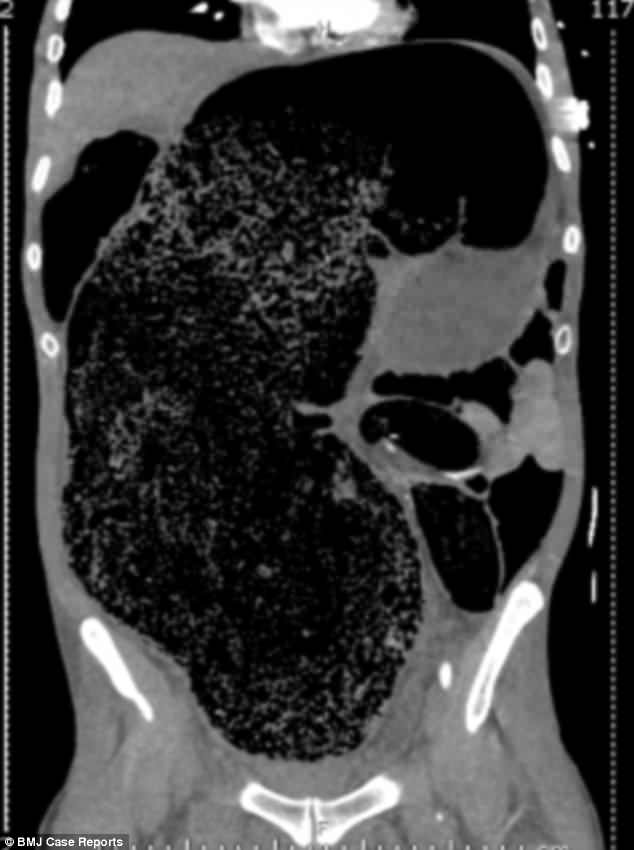

Ảnh chụp CT cho thấy lượng phân khổng lồ tích tụ trong khoang bụng bệnh nhân.